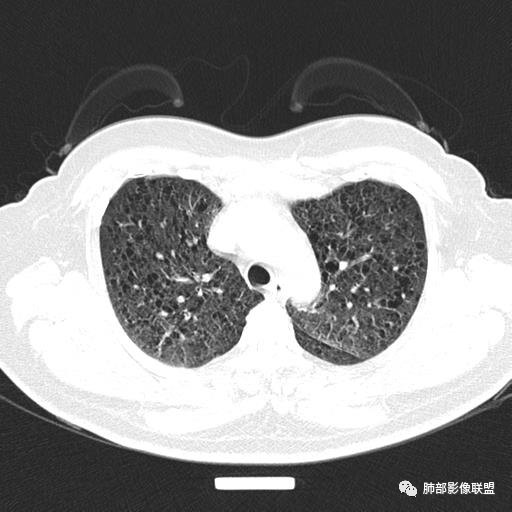

双肺弥漫囊腔,累及肋膈角,囊腔形态相对规则单一。

CT平扫示双肺弥漫分布大小不等囊状薄壁透光区,无内、中、外带分布差异,间质稍示增厚。拟LAM

中年女性育龄期妇女,咳嗽气喘,无吸烟史,有苯吸入史。影像:双肺弥漫均匀小囊腔,无明显分布优势,囊腔形态欠规则,壁薄,部分囊腔边缘血管征,伴双肺弥漫磨玻璃影,无结节,考虑lam,鉴别苯中毒肺损伤,囊腔多有分布优势,小叶中心分布为主,形态规整等

女,46,活动性气喘1年。苯吸入史半年。胸部CT:两肺弥漫囊腔,上至肺尖,下至肋膈角,形态类似小囊腔。考虑:LAM,鉴别LIP,BHD,PLCH等。

双肺弥漫大小不一薄壁含气囊腔,囊间肺组织正常,正常肺背景,肺尖肺底受累;青年女性,气喘,支持LAM

双肺多发大小相近的囊状影,分布趋势趋于一致,中年女性,考虑LAM。部分囊内见血管及分隔影,小叶中心性肺气肿代排

CT表现:双肺弥漫大小不等的薄壁囊腔,囊壁<2mm,外形规则,血管影多位于囊腔周围,囊腔之间肺组织正常,随着疾病进展到晚期,囊腔变大、增多,不可胜数,囊腔可融合成较大的囊,与肺气肿相似,形成间质性肺纤维化。部分病例可出现结节影。